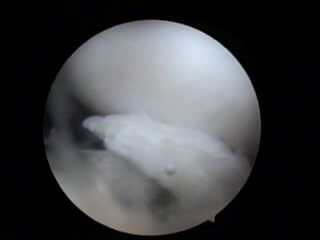

关节镜下清理术在指南中并不推荐,但对于有软骨剥脱、关节游离体的患者而言,如果出现有膝关节交锁症状,仍然不失为一种有效的治疗手段。

图3:关节镜手术可以清除游离的软骨碎片,达到减轻炎症和关节绞索的治疗目的